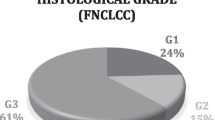

In this retrospective study, we investigated a total of 20 patients (10 males, 10 females, age: 59 ± 19 years old, range 18–87 years) who were pathologically confirmed to have STS and underwent FDG PET before any surgical intervention (total resection or biopsy), adjuvant chemotherapy, or radiation therapy at the National Hospital Organization Hokkaido Cancer Center between December 2010 and March 2016. The study population consisted of 17 patients with newly diagnosed STS and 3 with recurrent STS. Of the 20 patients, the tumors of three patients (two newly diagnosed and one recurrent) were diagnosed as low-grade (grade 1) based on Federation National des Centres de Lutte Contre le Cancer (FNCLCC) grading system, which is based on three pathological parameters (tumor differentiation, mitotic count, and tumor necrosis), and the tumors of another 17 patients were diagnosed as high-grade (grade 2, n = 7, five newly diagnosed and two recurrent; and grade 3, n = 7, seven newly diagnosed; unclassifiable between grades 2 and 3, n = 3, three newly diagnosed). The mitotic count information was not available for the unclassifiable patients. The patient histological types are summarized in Table 1. Tumors existed in the head and neck (n = 2), the thorax (n = 2), the abdomen (n = 7), an upper extremity (n = 2), or a lower extremity (n = 7). The cancer stage was IB (n = 3), IIA (n = 6), IIB (n = 3), III (n = 5) or IV (n = 3) based on the American Joint Committee on Cancer (AJCC) staging system ver. 7 (2011).